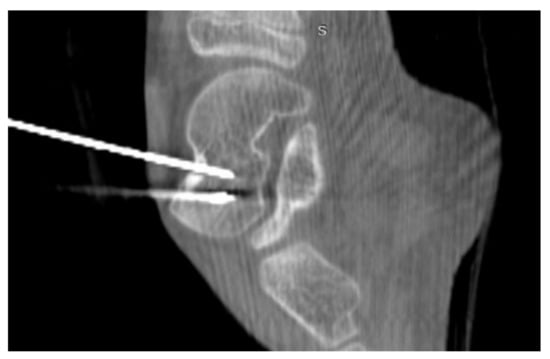

3.4. Case 4: OO Masking as a Fatigue Fracture